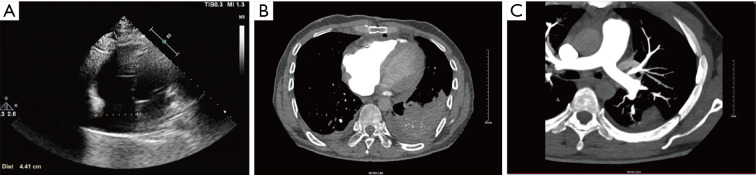

Case description: A 43-year-old man presented with progressive dyspnea, fatigue, and palpitations, imaging revealed a large mobile right atrial myxoma (78 mm × 52 mm) causing intermittent tricuspid valve obstruction and multifocal pulmonary emboli. Laboratory tests showed elevated B-type natriuretic peptide (BNP) and D-dimer levels. The patient was diagnosed with a benign cardiac tumor, PE, and New York Heart Association (NYHA) Class III heart function. Open-chest surgery with cardiopulmonary bypass resulted in successful tumor resection and emboli extraction. Postoperatively, the patient showed significant symptom improvement and no tumor recurrence at the 6-month follow-up. It is such giant right atrial myxomas that speak for the need for early diagnosis with surgical intervention.